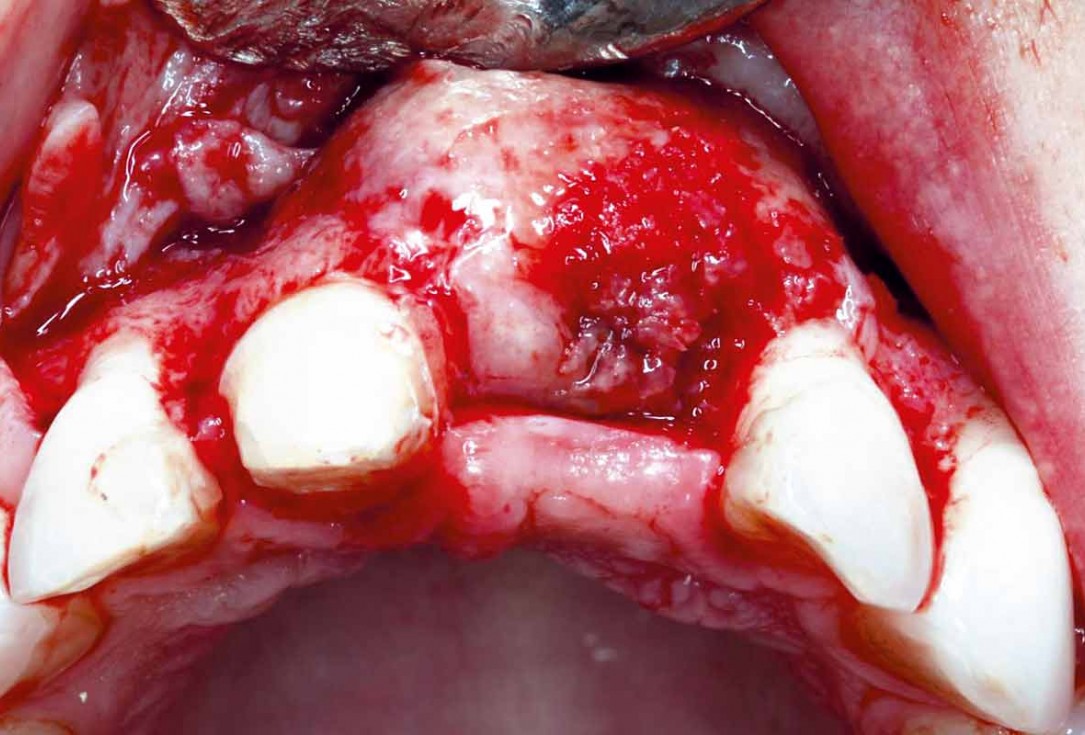

Implant placement and bone augmentation in the aesthetic zone using maxgraft® and permamem® - Dr. A. Puišys

Initial situation – Treatment plan: Replace the adhesive upper left central incisor bridge with a dental implant